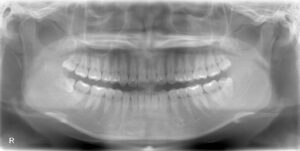

今回は上下同時に親知らずを抜歯しております。

画面向かって左側の一番奥の上下の歯です。